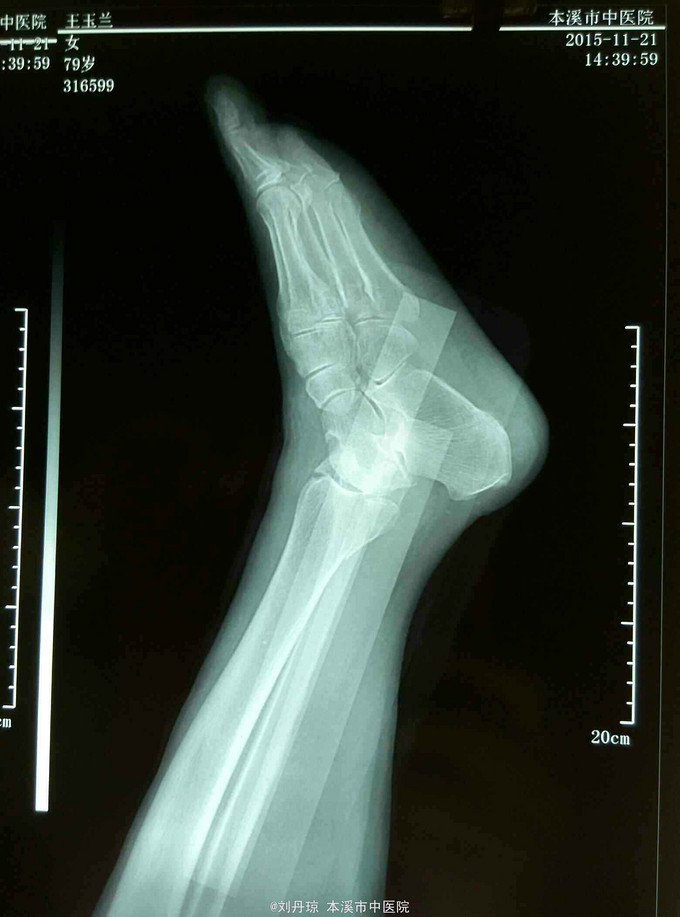

左踝关节刺痛,活动受限2小时。病史:患者2小时前下楼梯时不慎扭伤左踝,伤后左踝刺痛,活动受限,遂来我院门诊求治。既往:冠心病史20年,心梗病史1年。

左踝关节畸形,肿胀明显,压痛阳性,左踝关节功能障碍。足背动脉搏动清,足趾活动良好。辅查:DR:左踝关节骨折,三踝骨折移位明显。

诊断:左踝关节骨折 旋后外旋型IV度 治疗:手法整复,活血膏外用,夹板固定。接骨丹口服。